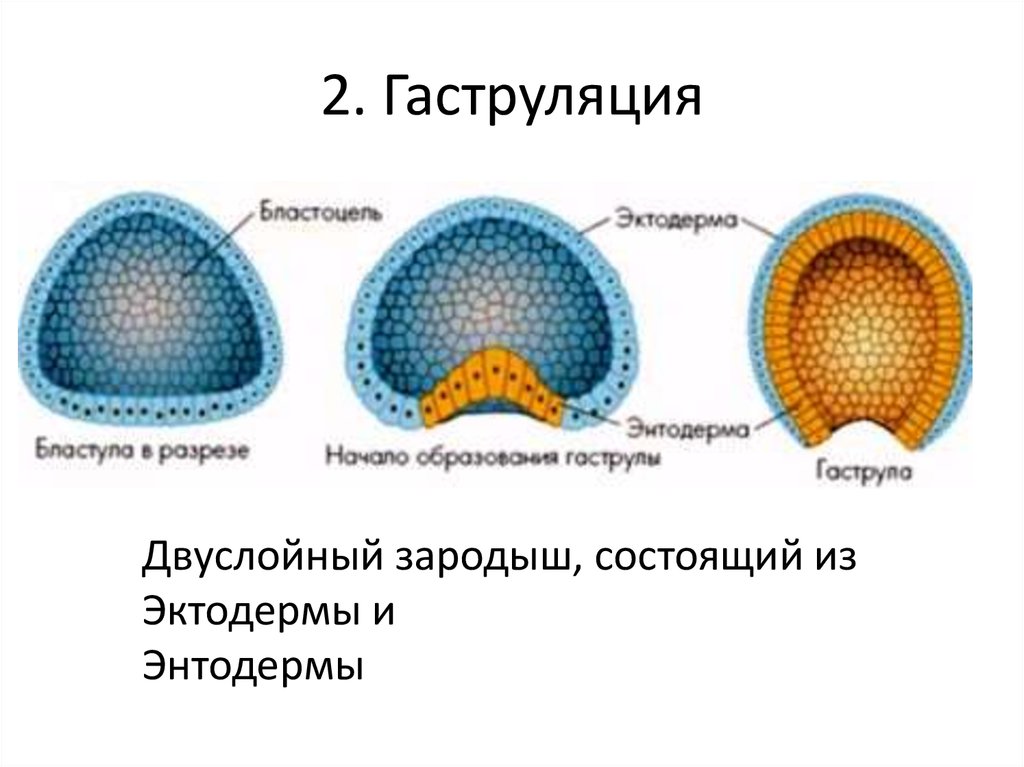

Эмбриональный период: Развитие эмбриона от зачатия до рождения